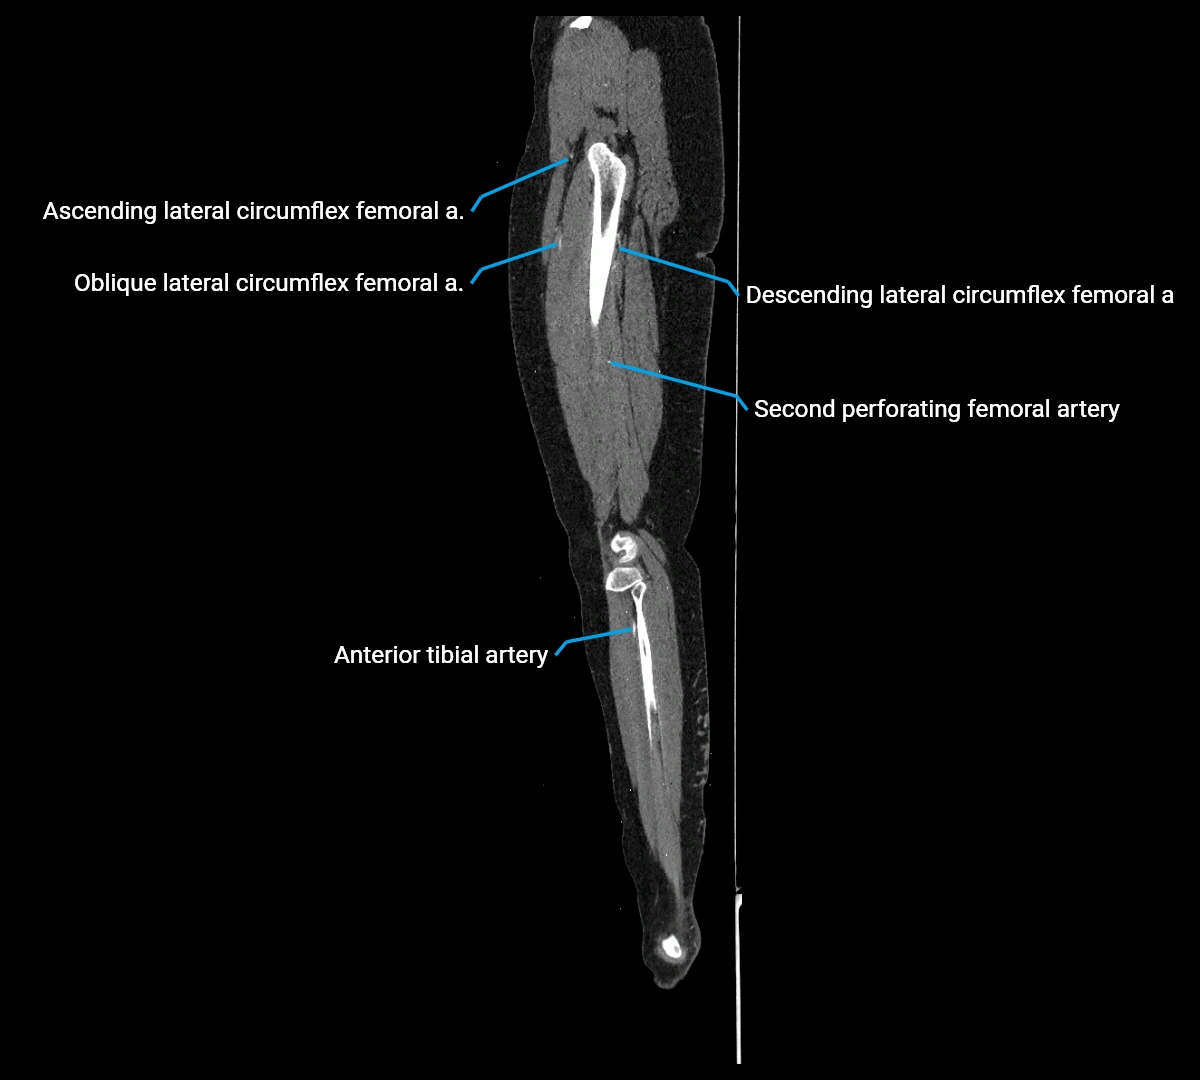

CT images

image

Contrast-enhanced CT (CTA):

• Gold standard for abdominal aortic imaging

• Provides excellent detail of lumen, wall, aneurysm, thrombus, and branch vessels

• Multiplanar and 3D reconstructions help in aneurysm measurement, stent graft planning, and dissection evaluation